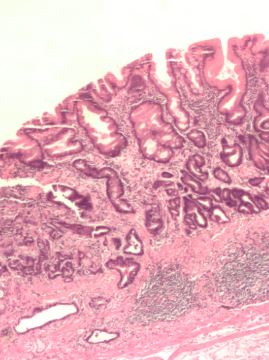

L’infiammazione gastrica rappresenta il primo segnale della presenza del batterio. Come spiega a Libero il Dott. Davide Moioli, specialista in chirurgia generale mini invasiva e bariatrica: “Il meccanismo principale attraverso il quale favorisce lo sviluppo del cancro gastrico è legato alla progressione istopatologica delle lesioni. L’infiammazione cronica indotta dal batterio altera l’equilibrio tra danno e rigenerazione della mucosa, favorendo mutazioni genetiche che portano allo sviluppo delle lesioni precancerose con una precisa sequenza: gastrite cronica, gastrite atrofica, metaplasia intestinale, displasia ed infine adenocarcinoma” .